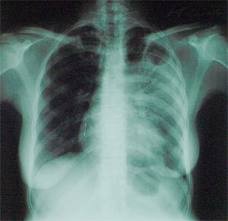

10 жителей Ленского района с заразной формой туберкулеза уклонялись от лечения

РИГ SAKHAPRESS.RU Прокуратура Ленского района провела проверку соблюдения прав граждан на охрану жизни и здоровья. Установлено, что 10 жителей Ленского района, страдающих заразной формой туберкулеза, уклоняются от прохождения полного курса лечения в специализированном медицинском учреждении. В соответствии со ст. 13 Федерального закона «О предупреждении распространения туберкулеза в Российской Федерации» лица, находящиеся под диспансерным наблюдением в связи с туберкулезом, и больные туберкулезом обязаны проводить назначенные медицинскими работниками лечебно-оздоровительные мероприятия. Пресс-служба Прокуратуры РС(Я): - В этой связи прокуратурой Ленского района в суд направлены заявления о принудительной госпитализации граждан, больных открытой формой туберкулеза. Решениями суда 9 исков удовлетворено, по 1 гражданскому делу производство прекращено ввиду добровольного исполнения ответчиком требований прокурора.